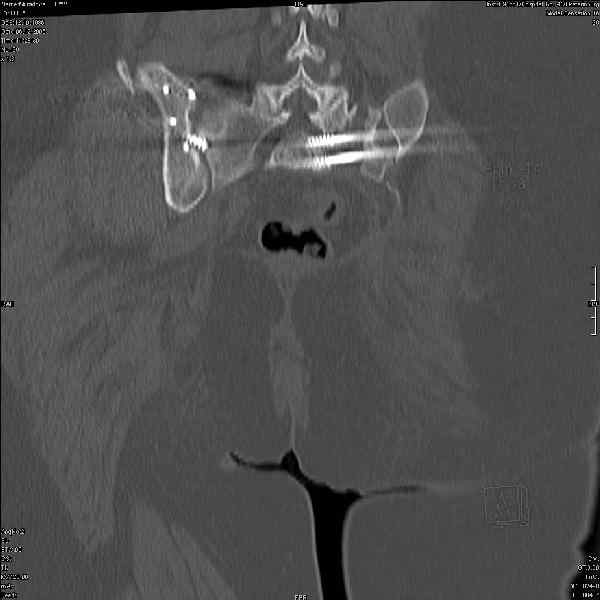

Могу сказать одно: миграция винтов и нестабильность синтеза левого подвздошно-крестцовогоо сочленения очевидна.

Вот цитата из статьи с odoс.ru:"Идеально было бы иметь винты диаметром 7 - 8 мм с довольно широкой резьбой в 50 - 80 мм. Также необходимы более длинные винты и, в общем, наиболее часто используемые размеры - между 90 и 150 мм." Думается, в этой статье вы найдете ответы на все ваши вопросы.

Забыл добавить, что ИХМО показан реостеосинтез более длинными винтами, с более широкой резьбой, с фиксацией за правое подвдошно-крестцовое сочленение.

Ув.коллега.Думаю, что реостеосинтез винтами бесперспективен.Пороз, наличие большого массива рубцовой ткани, невозможность создать жёсткую фиксацию в зоне ложного сустава крестца требуют изменеия вида остеосинтеза. Тут возможны два варианта.1) Открытый остеосинтез с атупластикой и фиксацией ВЧКО задним стержневым крестцовым аппаратом.2)Тоже самое, но фиксация 2 резьбовыми штифтами типа Штейнемана за заднюю ость подвздошной кости. От выдавливания крестца кпереди следует на этих гвоздяж зафиксировать реконструкционную пластину, которая винтами синтезирует фрагменты крестца.